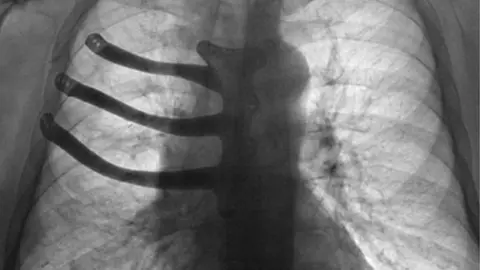

The prosthesis was inserted into Peter Maggs' chest after he had three ribs and half his breastbone removed.

The titanium implant was designed at Morriston and printed in Wales.

The titanium implant was made ahead, based on a design by Mr Goldsmith, who carried out the surgery with consultant surgeon Thomas Bragg.